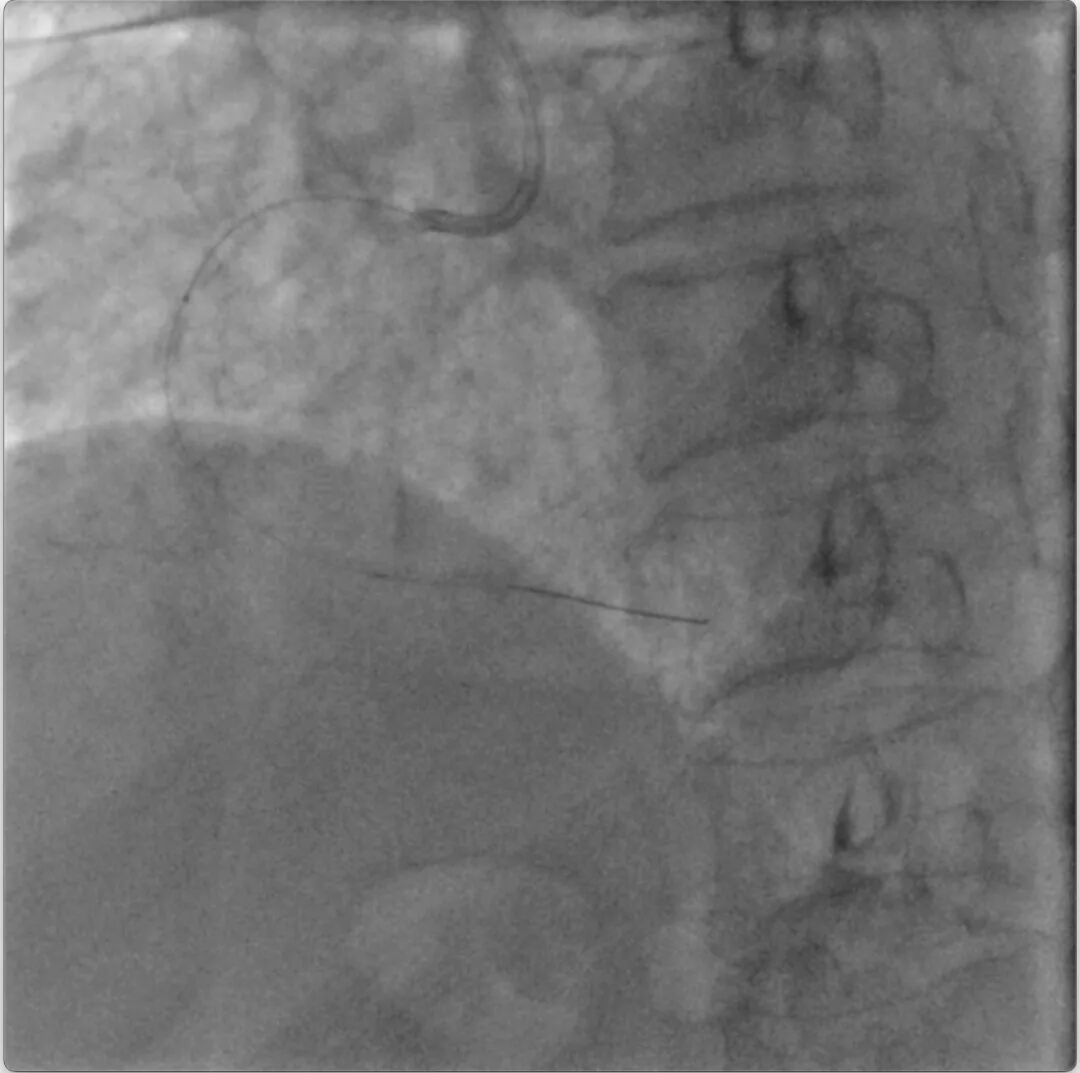

但此时再次尝试进入旋磨导丝,经过反复调整,最终将旋磨导丝送入右冠远端真腔(视频17)。随后旋磨顺利,1.25mm旋磨头,180000rpm通过中段阻力点(视频18)。交换为工作导丝后球囊扩张(视频19)。从右冠远端至近端串联置入2.5x30mm、3.0x30mm、3.5x18mm三枚支架(视频20)。